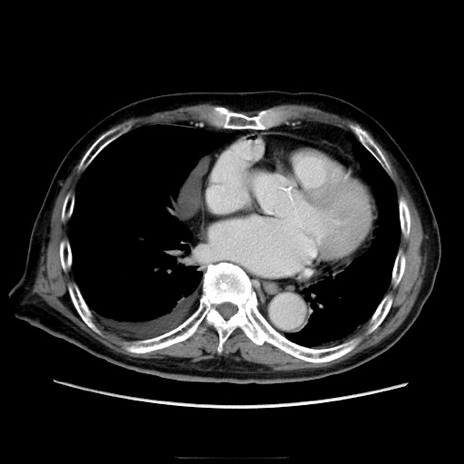

症例21(横断像)

【症例】70歳代男性

【主訴】腹痛

【現病歴】肝硬変・肝細胞癌にてかかりつけの方。約9時間前に食後より腹痛出現。症状が徐々に増悪し、嘔吐出現したため来院。

【既往歴】肝硬変、肝細胞癌(RFA、TACE後)

【身体所見】意識清明、表情苦悶様、BT 36℃、BP 129/78mmHg、P 88bpm、SpO2 97%(RA)、右上腹部から心窩部にかけて圧痛あり、反跳痛なし、筋性防御あり。

【データ】WBC 5800、CRP 0.16